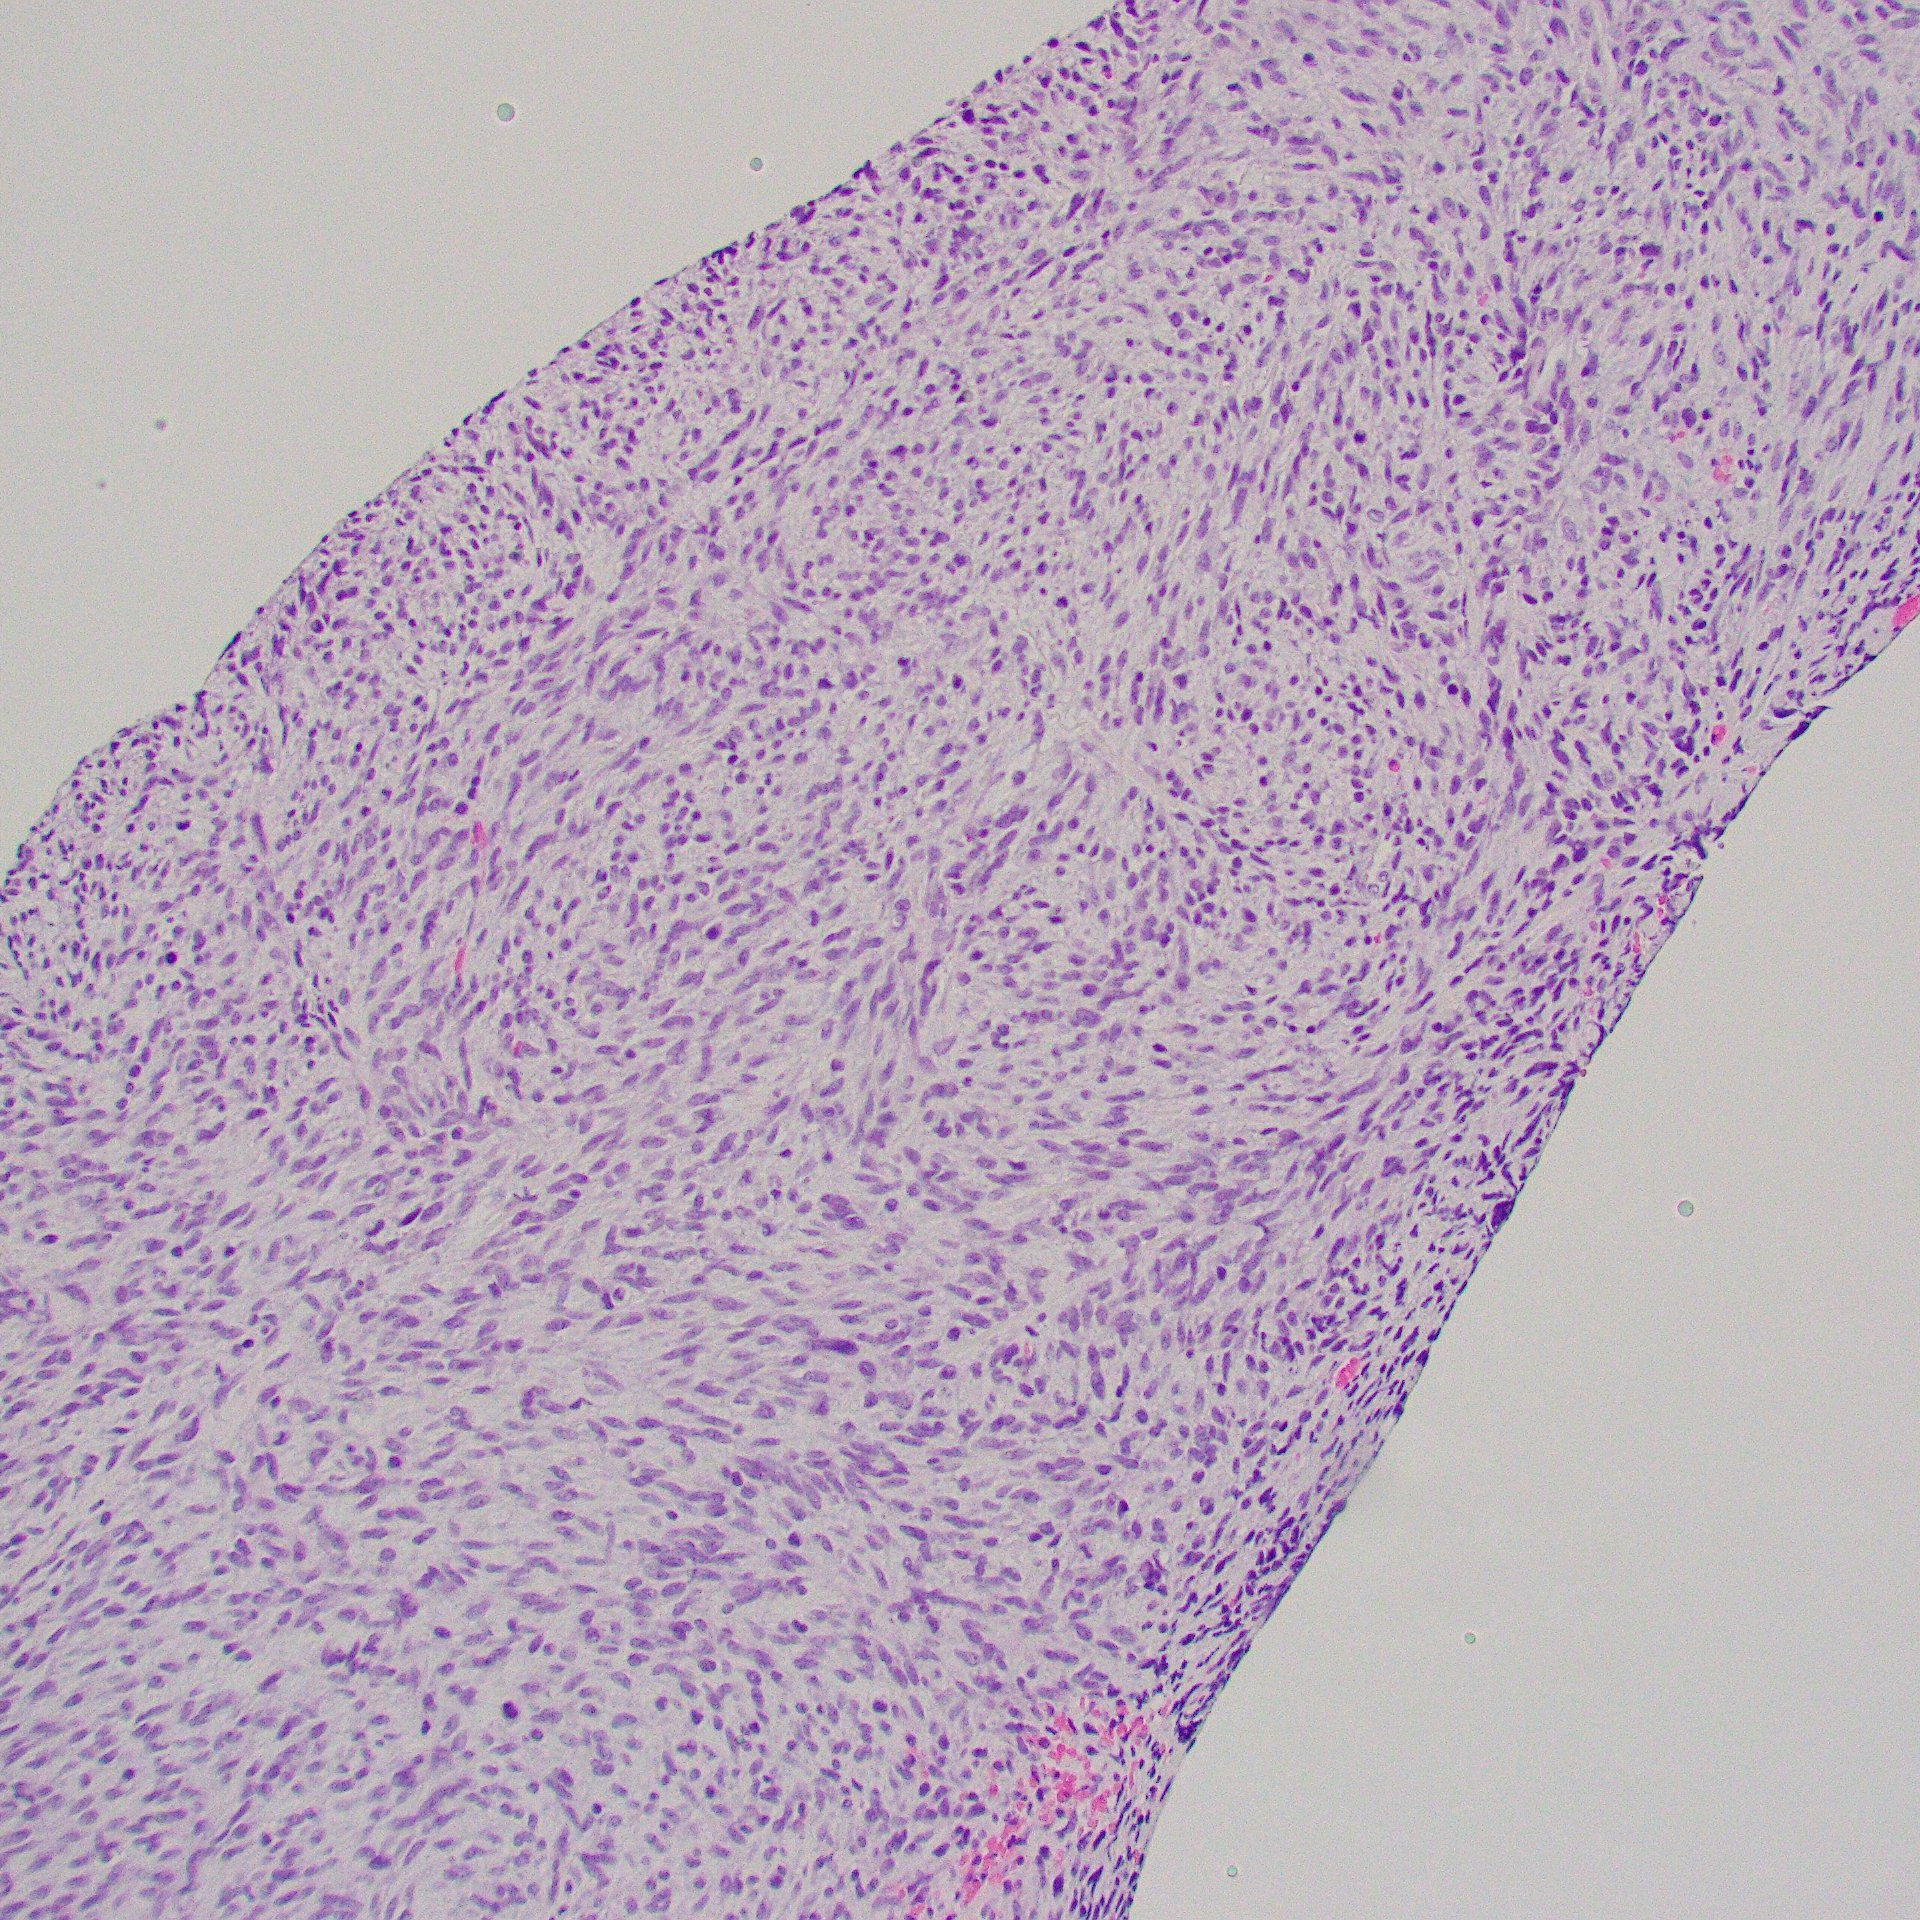

Hypercellular, monotonous spindle cell tumor, scattered mitoses; this case had TPM3::NTRK1 fusion

IHC: CD34, S100, and panTRK are diffusely positive; this case had TPR::NTRK1 fusion

NTRK1-associated Sarcoma